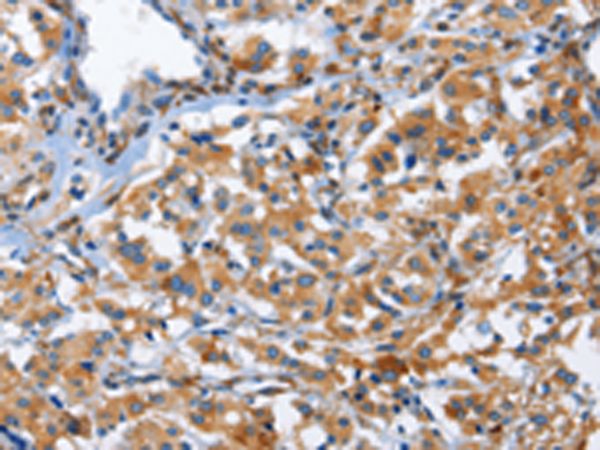

IHC positive control: |

Human thyroid cancer |

IHC Recommend dilution: |

50-200 |